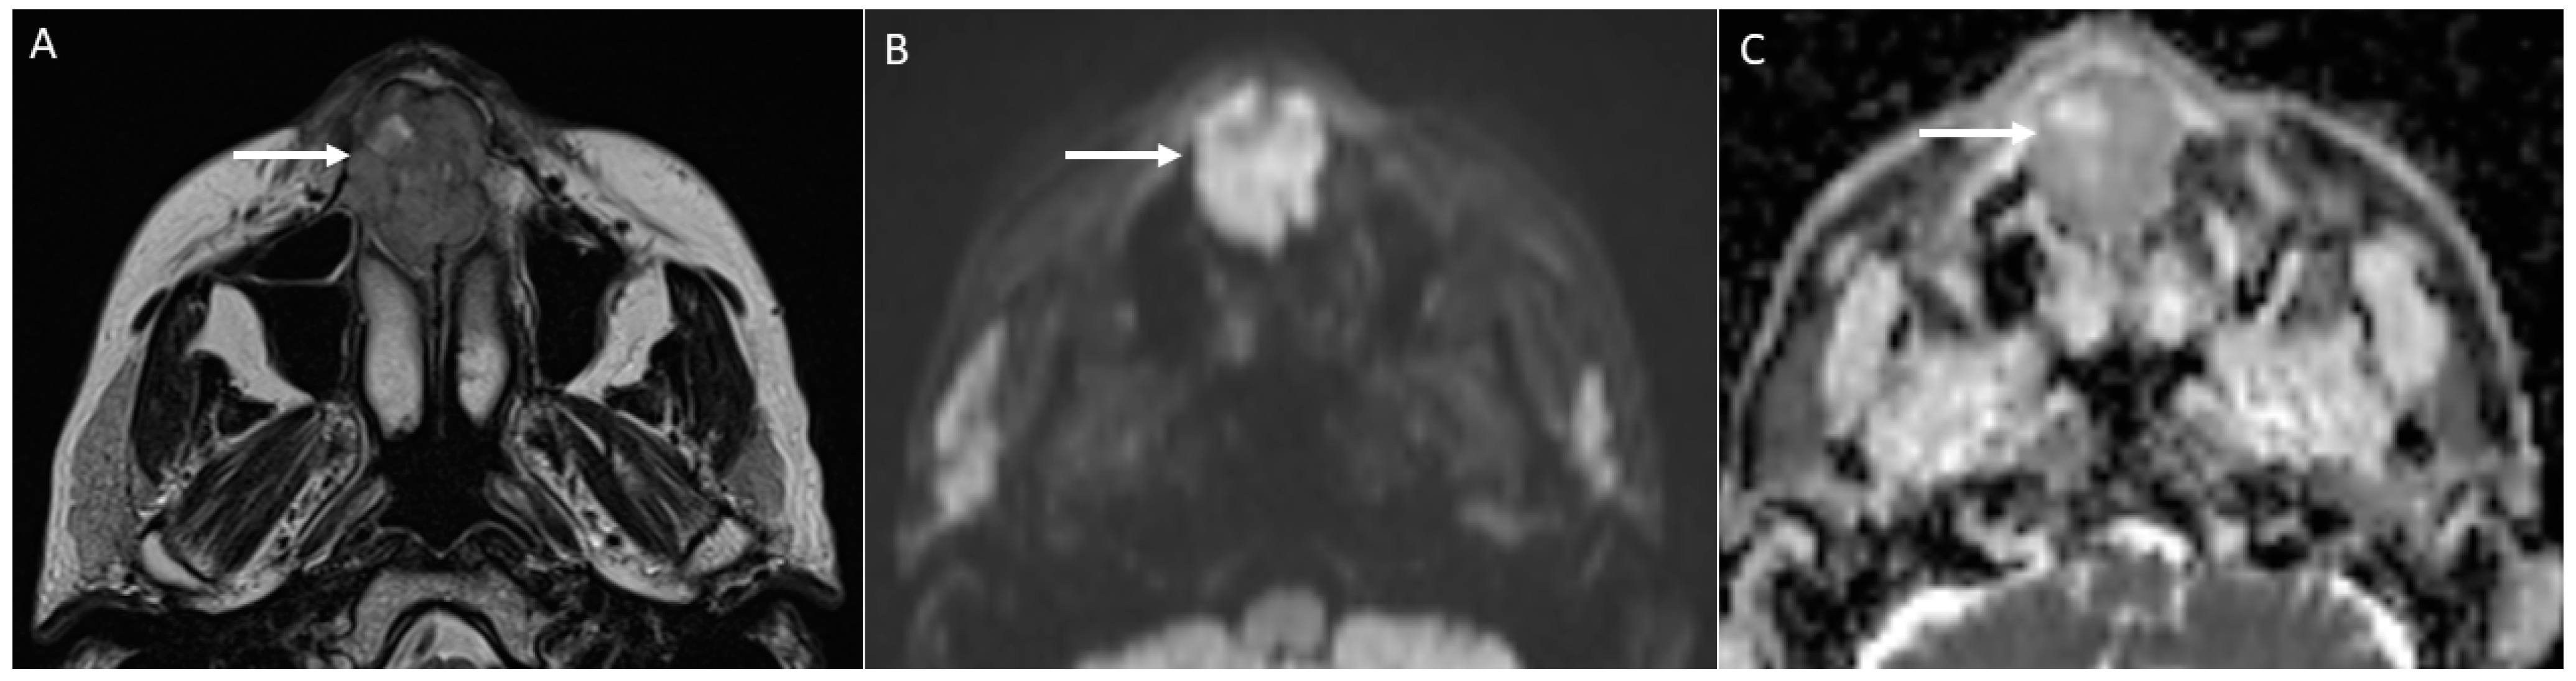

4.2.1. DWI

- Characterise oral lymphoma since it shows the lowest ADC values (<0.7 × 10−3 mm2/s) because of its high cellularity (strongly crammed lymphocytes) [30]. Abscesses and lymphomas can show an overlap of ADC values around 0.7 × 10−3 mm2/s. However, the differential diagnosis between them is normally carried out considering both the clinical assessment and unenhanced and enhanced morphologic MRI sequences. On the contrary, poorly differentiated carcinomas can assume ADC values similar to lymphomas supported by the increase in cellularity as the grade of the tumour increases, thus making the differential diagnosis more complex [34].